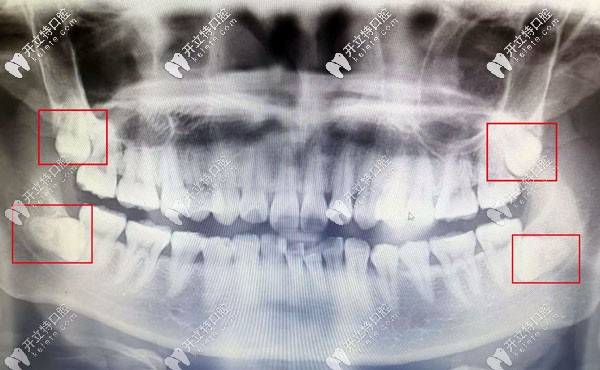

口腔的智齒反復(fù)發(fā)炎導(dǎo)致臉頰膿穿案例:

王女士已經(jīng)45歲,因左下智齒反復(fù)發(fā)炎未完全治療,導(dǎo)致智齒冠周炎伴向瘺,面部腫大,膿腫已經(jīng)把左側(cè)臉頰擊穿。

考慮到顧客患病時(shí)間久,導(dǎo)致智齒根尖局部炎癥范圍較大,智齒牙根距離下牙槽神經(jīng)管較近,面部膿腫組織需要切除,切除后的縫合難度也是比較大的。首先需要消除炎癥。

牙痛說(shuō)大不大,但是如果不夠重視,那后果也有可能會(huì)比較嚴(yán)峻。尤其是埋伏智齒,建議盡早拔除,有的不僅會(huì)發(fā)炎還是吸收正常牙齒的牙根,影響正常牙齒的健康。